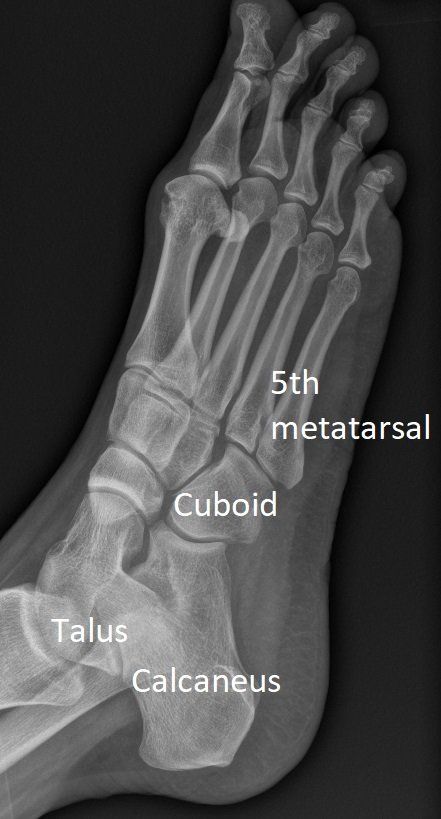

Normal Foot X-rays

Weight-bearing X-rays of the foot show bone alignment, arch height and joint health.